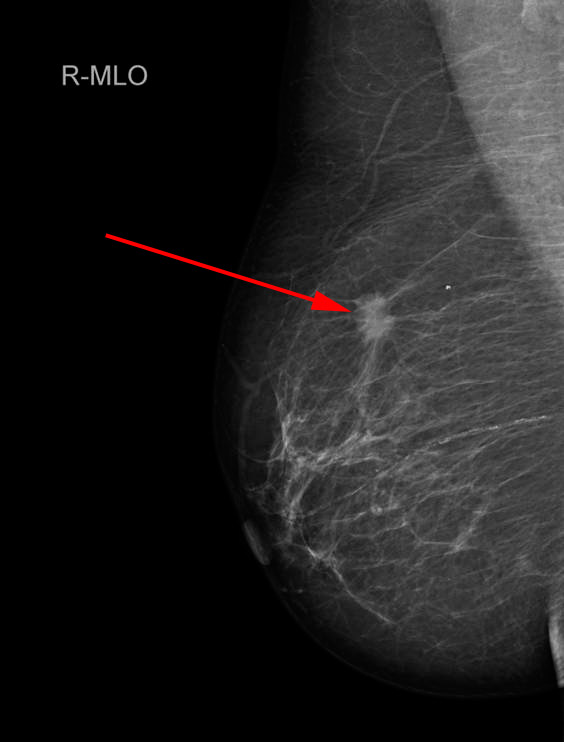

Mammografi. Spiculeret fortætning i højre bryst (rød pil). Vævsprøve viste, at det var en malign tumor.